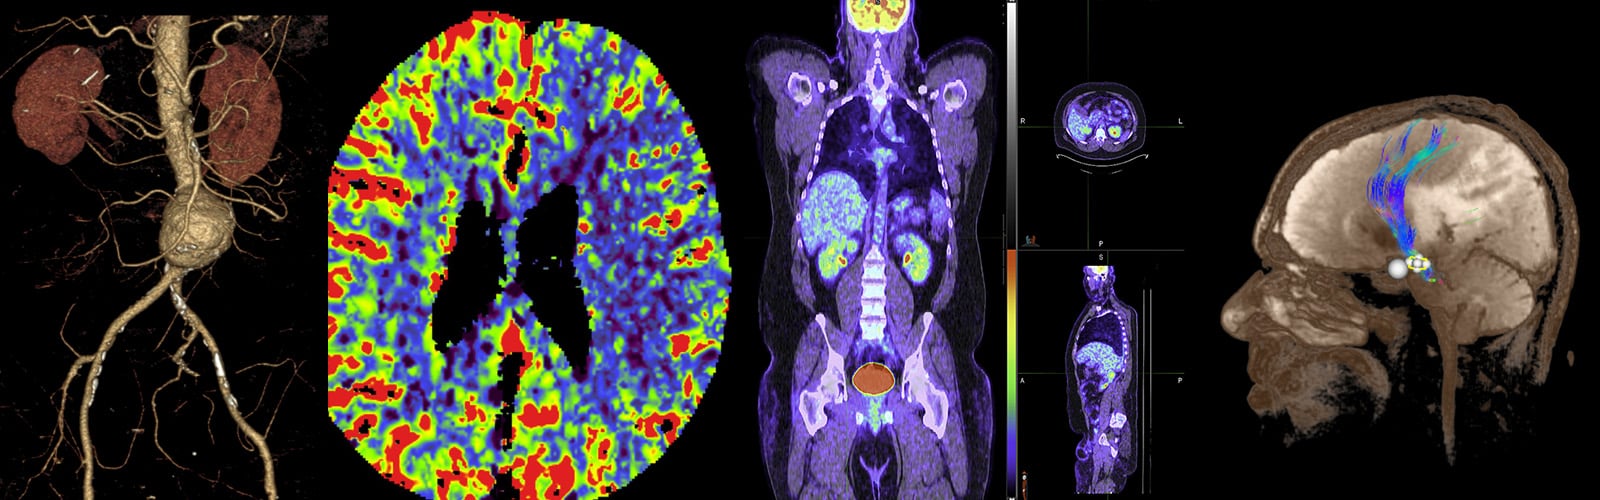

Radiology Research

Our mission is simple: to bring scientific advances in medical imaging to clinical application. Our current major areas of focus include Interventional Neuroradiology, Biomarker Development, Molecular Imaging, Nuclear Medicine Physics, and Cell Biology. Learn more.